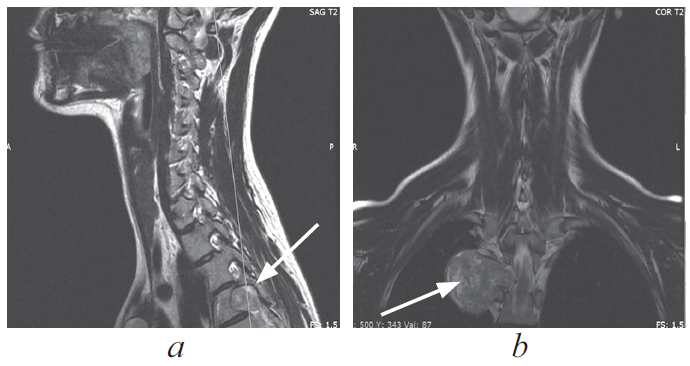

По данным магнитно-резонансной томографии грудного отдела позвоночника паравертебрально справа на уровне тел позвонков Th5 визуализируется образование гантелеобразной формы, размерами 9 × 39 × 35 мм, исходящее из правого корешка Th5; правое межпозвонковое отверстие расширено (рис. 1, 2).

Рис. 1. Магнитно-резонансная томограмма грудного отдела позвоночника, коронарная проекция, опухоль указана стрелкой

Fig. 1. MRI of the thoracic spine, coronal view, the tumor is indicated by an arrow

Рис. 2. Магнитно-резонансная томограмма грудного отдела позвоночника, сагиттальная (a) и коронарная (b) проекции, опухоль указана стрелками

Fig. 2. MRI of the thoracic spine, sagittal (a) and coronal (b) projections, the tumor is indicated by arrows